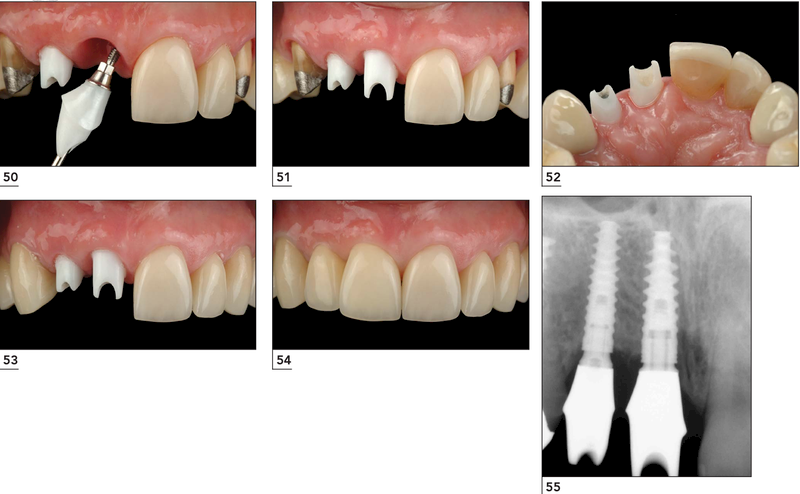

Sau khi mô mềm quanh vị trí cấy ghép lành, bác sĩ sẽ cắt chỉ và đặt trụ lành thương để tạo hình nướu tự nhiên